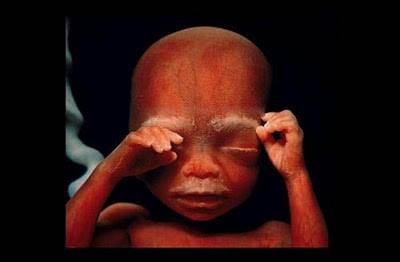

10-րդ շաբաթ: Կոպերն արդեն կիսաբաց են, իսկ մի քանի օր հետո ամբողջապես կձևավորվեն: